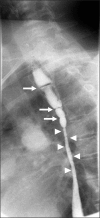

Esophageal candidiasis is commonly seen in immunocompromised patients; however, candida esophagitis induced stricture is a very rare complication. We report the first case of esophageal stricture secondary to candidiasis in a glycogen storage disease (GSD) 1b child. The patient was diagnosed with GSD type 1b by liver biopsy. No mutation was found in the G6PC gene, but SLC37A4 gene sequencing revealed a compound heterozygous mutation (p.R28H and p.W107X, which was a novel mutation). The patient's absolute neutrophil count was continuously under 1,000/µL when he was over 6 years of age. He was admitted frequently for recurrent fever and infection, and frequently received intravenous antibiotics, antifungal agents. He complained of persistent dysphagia beginning at age 7 years. Esophageal stricture and multiple whitish patches were observed by endoscopy and endoscopic biopsy revealed numerous fungal hyphae consistent with candida esophagitis. He received esophageal balloon dilatation four times, and his symptoms improved.